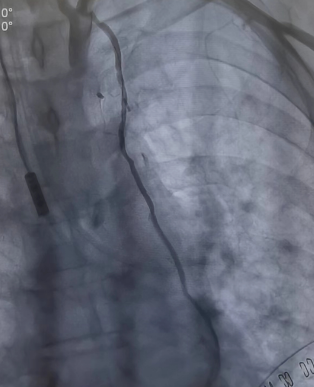

將兩者結(jié)合的手術(shù)方式就是雜交技術(shù)即“一站式微創(chuàng)”手術(shù)。手術(shù)先在左側(cè)胸壁做一個(gè)5-7厘米切口,進(jìn)行左胸廓內(nèi)動脈-左前降支(LIMA-LDA)架橋。接著進(jìn)行冠脈造影,檢查LIMA-LDA橋血管通暢度。同時(shí)在冠脈其他狹窄部位放入冠脈支架。

同期進(jìn)行冠脈放支架(檢查LIMA橋血管通暢)